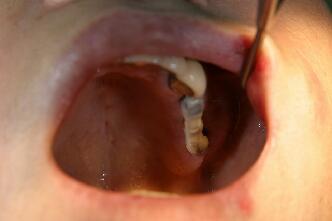

術前の口腔内写真

この方も上顎洞の下縁の骨が1~3ミリ程度しかなくソケットリフトでは不可能なのでサイナスリ フトの選択となる